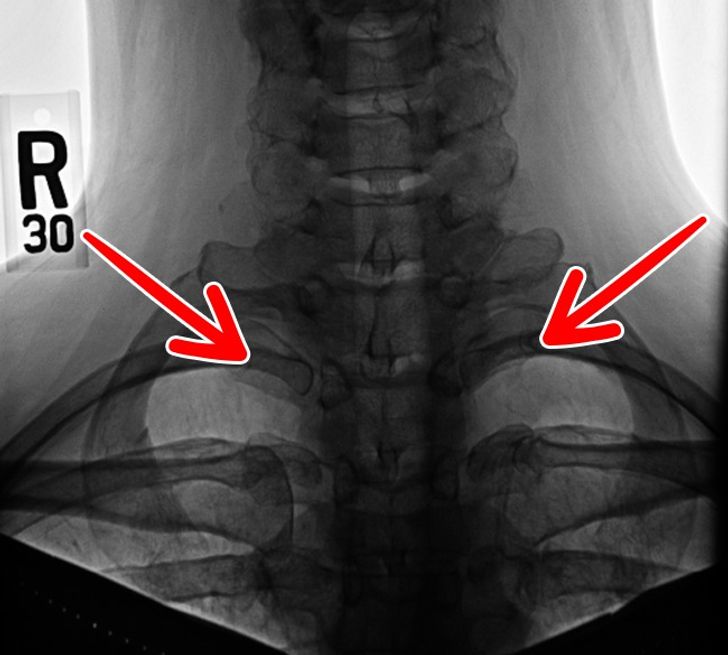

4. Żebro szyjne

Zespół żeber szyjnych, prawdopodobnie pozostałość po epoce gadów, nadal występuje u mniej niż 1% populacji. U niektórych osób znajduje się tylko po lewej lub prawej stronie, a u innych po obu. Często powodują one problemy z nerwami i tętnicami.